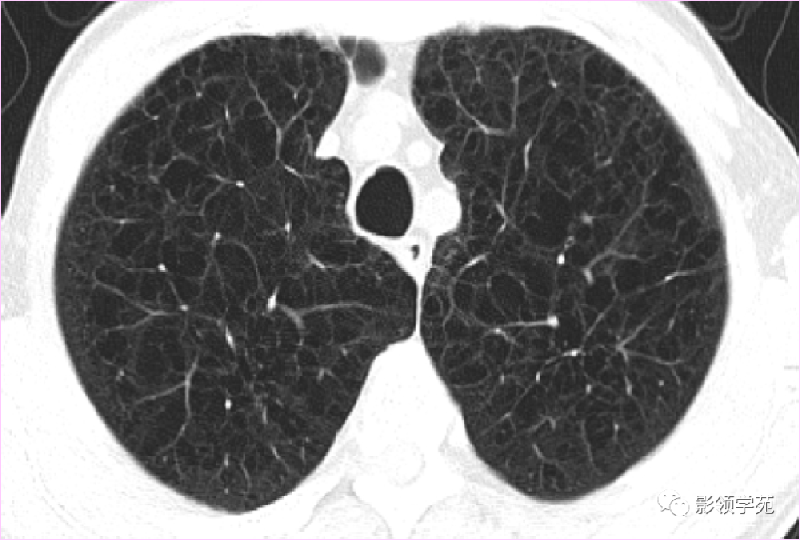

肺出血(片状、边缘模糊)

(5)肺内多发结节,由肉芽肿和炎症构成,较大结节发生空洞,多数结节边缘见有血管进入,则要考虑到肺韦格氏肉芽肿可能。